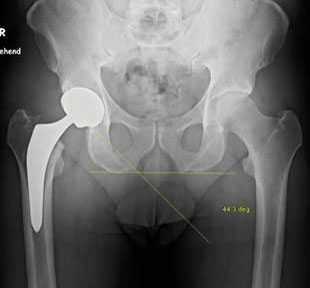

Пациентка Ж, 28 лет. Обратилась в К+31 в октябре 2017. Страдала врождённым подвывихом головки правого бедра, лечение в детсве не проводилось (на тот момент рутинного УЗИ скрининга в СССР не было, а к детскому ортопеду направляли не всех детей). В возрасте 23 лет отметила появление болей в области правого тазобедренного сустава. На протяжении последних 3 лет отмечала нарастание болевого синдрома, нарушение походки, ограничение амплитуды движений и постепенное укорочение конечности. Обратилась в К+31, выполнены рентгенограммы на которых визуализируется коксартроз 3 ст справа на фоне дисплазии правого тазобедренного сустава.

Принято решение о выполнении тотального эндопротезирование правого тазобедренного сустава протезом бесцементной фиксации пара трения керамика-керамика, с восстановлением длины конечности.

Снимки после операции. Длина конечности восстановлена. В сравнении со снимками до операции хорошо видно как восстановилось нормальное положение тазового кольца и поясничного отдела позвоночника. Пациентка была прооперирована в день поступления, переведена из РАО через 2 часа после операции, активизирована через 6 часов после операции. На вторые сутки обучена ходьбе с дополнительной опорой на костыли.